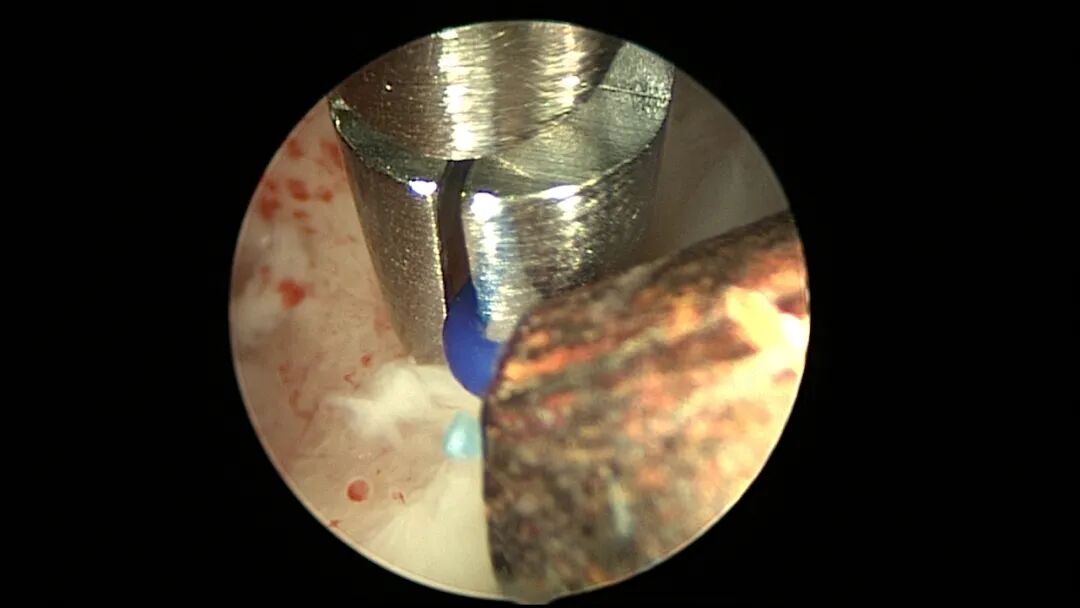

操作步骤描述:宫腔检查镜可完成操作,扩张宫颈至7号扩宫棒,检查镜能轻松通过,避免镜鞘与节育环纵臂在宫颈管形成卡压及筷子效应,影响操作,或卡压摩擦阻力大带出节育环。可用单级电针在宫底扎出小凹坑做标记或作为置入挂钩的隧道(不是必须的)。将挂钩用异物钳直视下送入宫腔,或用中弯钳盲视下送入宫腔,异物钳夹持挂钩将倒钩端插入宫底肌层,越过倒钩。用环尾丝或不可吸收线在节育环顶端打结,形成一个线圈,直径约0.5cm~1cm,结打在线圈旁边,便于夹持操作。将环装回推杆送入宫腔,再夹住节育环固定线圈抵紧宫壁稍旋转就可以将线圈滑进挂钩缺口,挂到挂钩上,可再次向宫底推送挂钩少许,不必夹闭挂钩缺口,重力作用和内膜生长都会阻止线圈脱出,可以用电针电凝挂钩周围组织,进一步防止挂钩脱落。异物钳原位固定节育环,退出宫腔镜,距宫颈外口0.5cm~1cm剪断剩余尾丝。宫颈扩张到9号扩宫棒,冷刀系统异物钳夹持挂钩及线圈也可完成以上操作。

取胚术后丝线挂钩固定节育环图片及视频

子宫腺肌症内膜息肉切除后丝线挂钩固定曼月乐并电凝图片及视频

异常子宫出血内膜增生节育环尾丝挂钩固定曼月乐图片及视频

挂钩固定注意事项:月经干净3~7天手术,此时内膜最薄,利于挂钩固定到子宫肌层,如果内膜较厚,最好用负压吸引器去除内膜,暴露基底层,挂钩才能放置到位,也避免内膜掀起、出血等影响操作。挂钩尖端能轻松在子宫壁上粘附,然后调整钳的位置,将挂钩插入到宫底肌层。也可以在体外连接好挂钩和节育环,同时送入宫腔,异物钳在宫腔夹持挂钩并插入宫底肌层。术后复查B超节育环距宫底距离可能较大,个别达3cm左右,跟子宫大、宫壁厚、外加挂钩长度及线圈长度之和较大有关,保持这个距离不再延长即为手术成功。